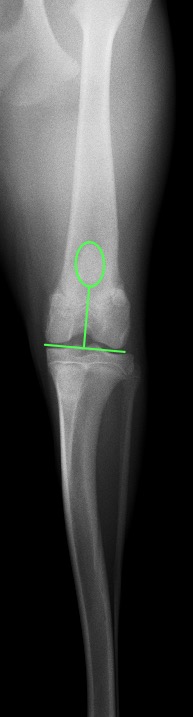

次の2枚の写真はパテラアルタのある今回の子と正常の子の膝関節と膝蓋骨の位置を示したものです。

パテラアルタの膝関節